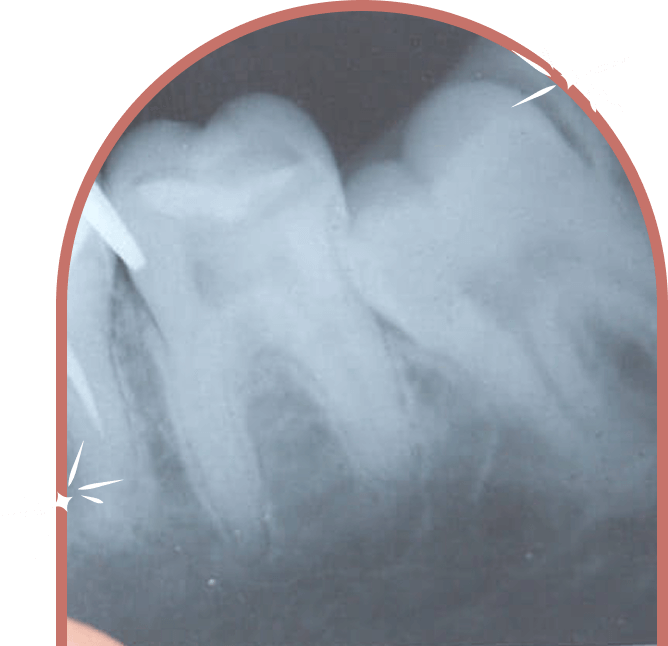

Clinical Results

Fotona’s SSP (Super Short Pulse) and SWEEPS (Shock Wave Enhanced Emission Photoacoustic Streaming) laser technologies penetrate deep into the root canal system, eliminating bacteria and biofilm from areas traditional tools often miss-resulting in superior cleaning and reduced risk of reinfection.

Laser-assisted deep cleaning and disinfection.